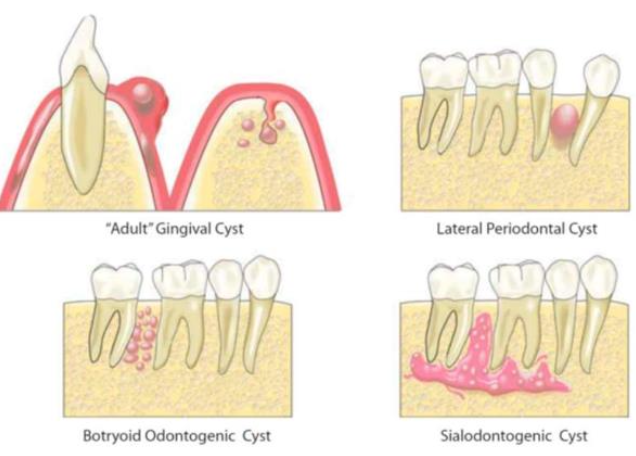

| Gingival Cyst of the adult (LPC 長出來) | 下顎premolar、canine facial 牙齦 | 40-60y | 藍色(bluish)、藍灰色(DeepSkyBlue-gray)  |

||

| focal plaques | |||||

focal plaques |

| Lateral Periodontal (LPC) | 下顎 premolar、canine、lateral incisor lateral root 表面 | 40-70y | |||

類似 OKC,但推開牙齒  |

| Botryoid Odontogenic Cyst (BOC) | 多囊 LPC | ||||

| Glandular Odontogenic Cyst (GOC) | - | 下顎前牙 | 46-51y | 跨中線、無 MAML2 | |

復發、局部侵犯性,吃 cortical bone  |

| 杯狀細胞, cilia, focal plaques | |||||